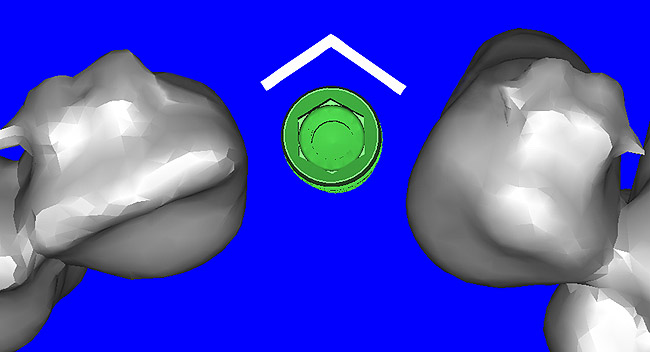

Using the interactive treatment-planning software application, the scan data was assimilated and both potential lateral incisor implant receptor sites were evaluated. It is a.combination of the data and the methodology used to interpret the data that is the basis for defining a new paradigm in diagnosis and treatment planning. Proper evaluation of these images and correct use of the interactive treatment-planning software tools is essential in creating a decision tree of treatment options. First, the data from the scan was reformatted into panoramic, axial, and cross-sectional images. The undistorted cross-sectional images revealed the residual alveolar bone in the area of the right lateral incisor. Then, a simulated schematic implant was placed within the bone with an abutment extension to help visualize the connection to the restorative position of the tooth (Figure 4A). The Triangle of Bone® (TOB), a concept developed by the author to analyze bone quality, quantity, and disposition at prospective dental implant sites using CBCT scans, aided in determining available bone volume by defining a “zone” for proper implant placement18,19 (Figure 4B).

After reviewing the CT data and the decision tree, the bone within the “zone” of the TOB was evaluated and found to be satisfactory for implant placement. Because the goal of implant dentistry is not the implant but the tooth that is placed, true restorative-driven implant dentistry must begin with the assumption that the implant position should remain consistent with the tooth it is replacing, and the final implant-supported restoration.12,22-26 The TOB aids the clinician in understanding the link between the implant position and the desired restorative goal. The base of the geometric shaped “zone” is visualized by starting at the widest area of alveolar bone facially and superiorly. The apex of the triangle is positioned to bisect the alveolar crest (Figure 4B). The TOB, the overlay in the cross-sectional image, reveals whether adequate bone is available for implant placement. It also helps to identify concave facial bone defects, and accurately determine the width of bone at the crest. The author r.commends using an interactive software application that provides the necessary measurement tools to accurately assess the bone anatomy.

Figure 4a  CT scan data was input into the treatment-planning software, which allowed (A) placement of a simulated implant and (B) the determination of the “zone” for proper placement.

Figure 4a

Figure 4b  CT scan data was input into the treatment-planning software, which allowed (A) placement of a simulated implant and (B) the determination of the “zone” for proper placement.

Figure 4b